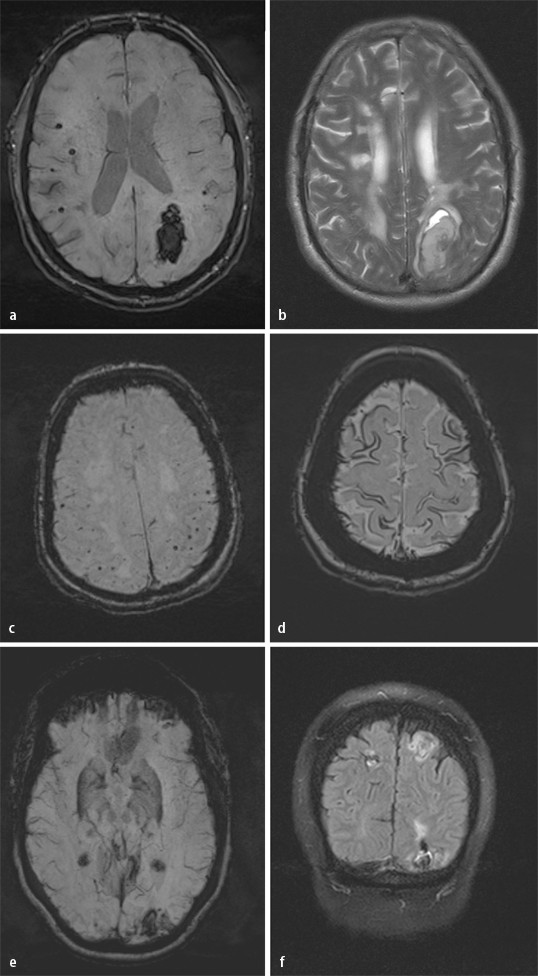

Zerebrale Amyloidangiopathie Und Demenz Springerlink

Mikroangiopathien Und Leukodystrophien Als Differenzialdiagnosen